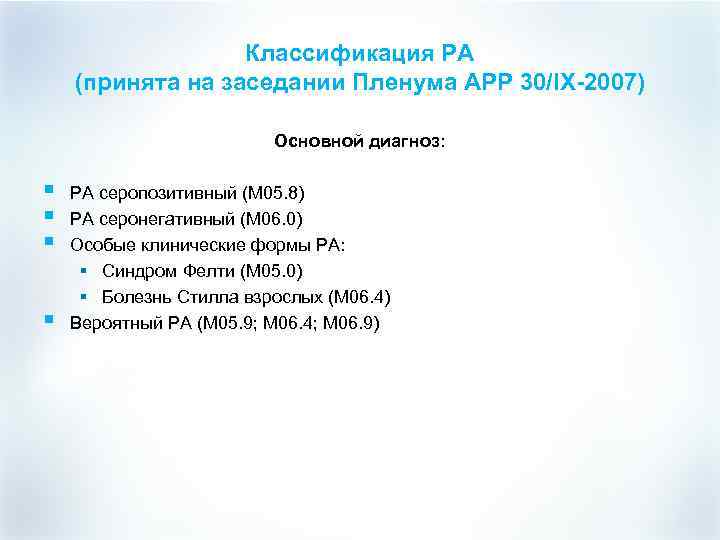

Классификация РА (принята на заседании Пленума АРР 30/IX-2007) Основной диагноз: § § РА серопозитивный (М 05. 8) РА серонегативный (М 06. 0) Особые клинические формы РА: § Синдром Фелти (М 05. 0) § Болезнь Стилла взрослых (М 06. 4) Вероятный РА (М 05. 9; М 06. 4; М 06. 9)

Классификация РА (принята на заседании Пленума АРР 30/IX-2007) Основной диагноз: § § РА серопозитивный (М 05. 8) РА серонегативный (М 06. 0) Особые клинические формы РА: § Синдром Фелти (М 05. 0) § Болезнь Стилла взрослых (М 06. 4) Вероятный РА (М 05. 9; М 06. 4; М 06. 9)